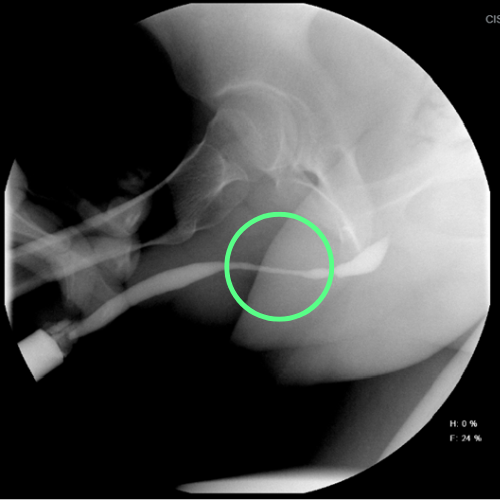

Imagen de cistouretrografía con referencias que permiten identificar un segmento uretral con calibre normal y uno con calibre reducido.

Cistouretrografía que revela una estenosis de uretra. El asterisco (*) marca una porción de uretra con calibre normal, mientras que el círculo un segmento más estrecho.